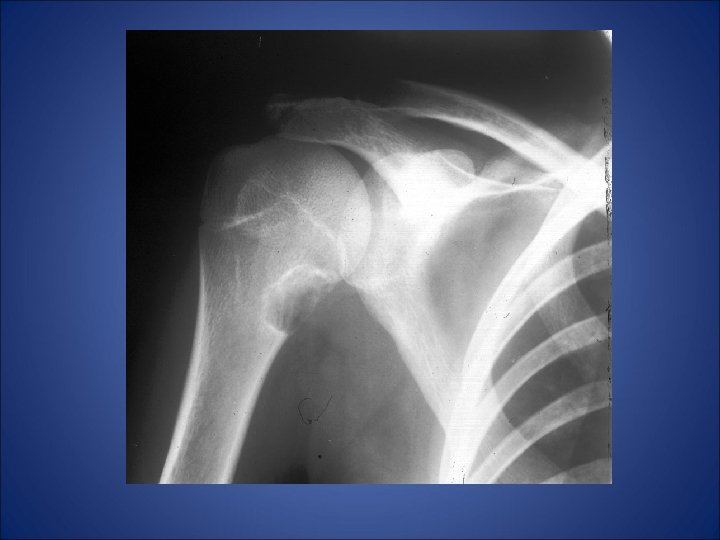

• A 26 yrs old male presented with complaint of pain in left shoulder after lifting a heavy weight. • His x-ray of left shoulder was taken which revealed…

Shows slightly expansile, septated lytic lesion is present involving the proximal 1 /3 rd of the left humerus. The margins are not sclerotic. The epiphysis appears uninvolved.

The most likely differentials would be: • Unicameral bone cyst • Aneurysmal bone cyst • Enchondroma • Fibrous dysplasia • Myxoid fibroma.

Radiolucent lesion with expanded cortex arising in medullary canal of metaphysis of humerus -aneurysmal expanded appearance of cortex is contained by periosteum & thin shell of bone; -Marked cortical thinning and erosion and periosteal elevation

UNICAMERAL BONE CYST • The unicameral or simple bone is a common lytic bone lesion. • It has been suggested in the past that the lesion results from prior trauma, infection, or neoplasia. Current theories suggest that the lesion results from venous obstruction during bone growth. The fluid within simple bone cysts has a composition similar to serum. • Simple bone cysts are asymptomatic unless complications such as fracture arise. • They are usually found in young people in the first few decades of life and are more common in males (M: F 3: 1).

• The most common locations are in the metaphyseal regions of long tubular bones, especially the proximal aspects of the humerus and femur and the tibia, which account for 60 -75% of cases. • Diaphyseal involvement is uncommon and epiphyseal extension is exceedingly rare. The axial skeleton is uncommonly involved. • Simple bone cysts are very rarely multiple within the same patient. On serial radiographs the lesion may enlarge with time. • Complications of simple bone cysts include fractures, cementation with fibrous material and a change in their radiographic appearance, and possibly malignant transformation to chondrosarcoma, liposarcoma, or osteosarcoma.

• RADIOLOGY: • Plain film: Characteristic location as described above. The classic plain film location is of a centrally located, mildly expansile, lytic lesion. • Some simple bone cysts may appear multiloculated and a thin sclerotic margin is usually present. With pathologic fracture the "fallen fragment" sign is a classic. • CT: May better delineate the extent of the lesion. Reports of gas within cysts detected at CT have occurred ("pneumatocysts") with gas-fluid levels. • Tc 99 Scintigraphy: Heterogeneous increase in activity involving the proximal third of the left humerus. • MRI: (HUMERUS) An expansile, lobulated lesion is present involving the metaphysis and proximal humeral shaft. The signal is T 1 WI dark and T 2 WI bright, uniformly and there is no evidence of enhancement.

• Thus in our case… • Metaphyseal expansile lytic lesion which is centrally located and a multiloculated appearance not involving epiphysis without any calcification with surrounding normal bone in the proximal end of humerus in a 26 yrs old male … • Mostly likely diagnosis is • UNICAMERAL BONE CYST